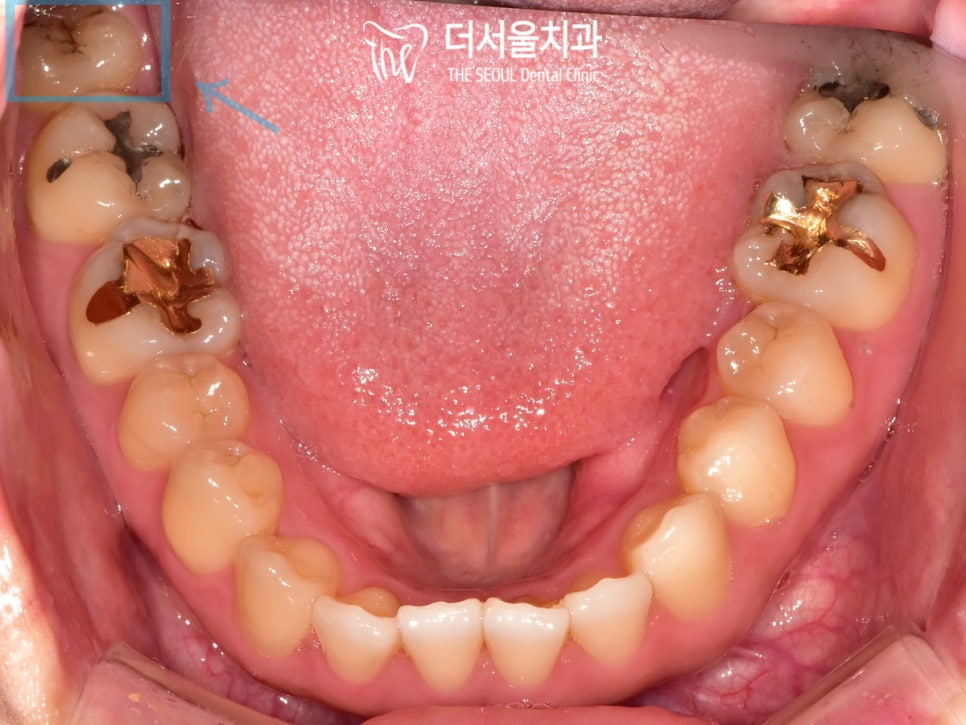

제가 어제 작성한 글을 미리 보고 오시면 많은 도움이 되실 겁니다. 오늘 소개해 드릴 케이스는 충치치료 증례입니다. "보통 충치치료는